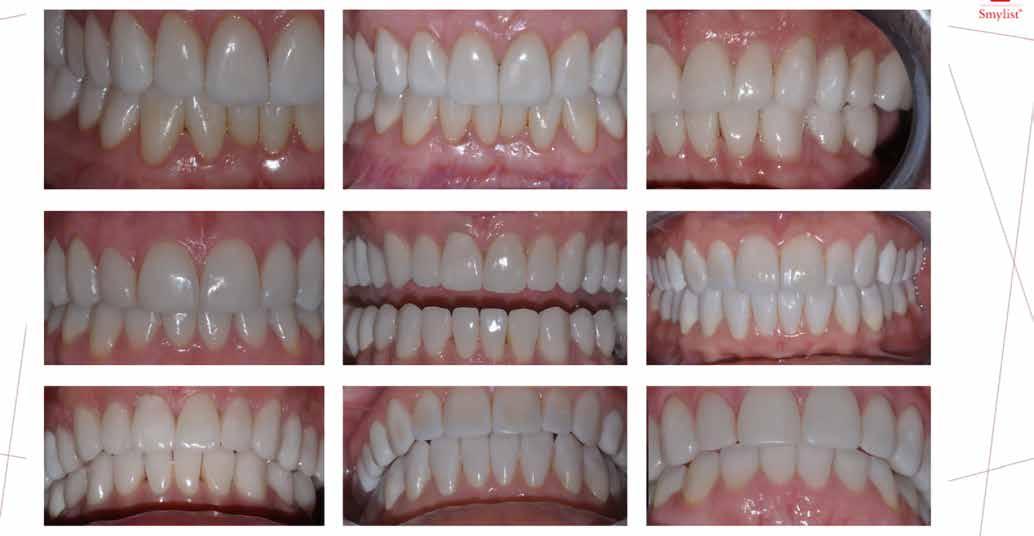

A kezeléstervezés egyik legfontosabb lépése a mock-up elkészítése. A mock-up alapjául szolgáló wax-up-ot (felviaszolás) is ugyanolyan részletességgel kell a fogtechnikusnak elkészíteni, mintha azok már a végleges fogpótlások alapjául szolgáló mintázatok lennének. A mock-upnak nagyon pontosan kell illeszkednie, valamint a tervezett fogpótlás meg-

jelenését is rendkívül élethűen kell reprezentálnia. Ahhoz, hogy a páciens mock-uppal kapcsolatos első benyomásai kedvezőek legyenek, a mock-up színének a páciens „szemfehérjének” színével meg kell egyeznie. A kezelési cél páciens által történő elfogadása és a tervezett eredménnyel kapcsolatos „wow-effektus” kialakulása nagyban függ a páciensben az első megtekintés során kialakult első benyomásoktól.

Az eddigi tapasztalataink szerint a páciensek jelentős többsége egyértelműen kifejezi az elégedettségét, ha a mock-up megfelel az eredeti elképzeléseiknek. A bemutatásra kerülő esetben is ez történt. A tervezett végeredmény megtekintését követően a páciens azonnal kérte az általunk javasolt kezelési tervben ismertetett beavatkozások elvégzését. A héjak alapanyagául az Ivoclar Vivadent által gyártott A1-es színű Telio CS kerámiát javasoltuk. Az anyagválasztás hátterében az állt, hogy ez az anyag nagy keménységgel rendelkezik, valamint az, hogy a felszínét nagy simaságúra lehet polírozni. A páciens rendkívül fiatal életkora is azt a terápiás koncepciót erősítette, hogy a kezelés során lehetőség szerint kizárólag non-invazív beavatkozásokat alkalmazzunk.

A kezelés során az jelentette a legnagyobb kihívást, hogy a héjakkal ellátott fogak élethűen utánozzák a természetes fogazat megjelenését. A fogpótlás színének, valamint a restaurátumok felszíni textúrájának és alakjának harmonikusan kell a páciens arcesztétikájához és karakteréhez illeszkednie.